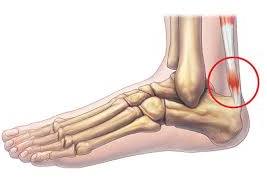

족저근막은 발바닥의 아치 모양 곡선을 유지하고 발에 전해지는 충격을 흡수하는 스펀지 같은 역할로 발바닥 근육을 감싸고 있는 얇은 막입니다. 이곳에 지속적인 충격, 마찰이 전달되면 결국 염증이 생겨 살살 걸어도 발이 아프게 됩니다.

물리적인 자극이 지속될수록 발뒤꿈치뿐 아니라 발 안쪽까지 아프고 쑤시는 증상을 보이기 때문에 가급적 빨리 치료할수록 경과도 좋은 편입니다.